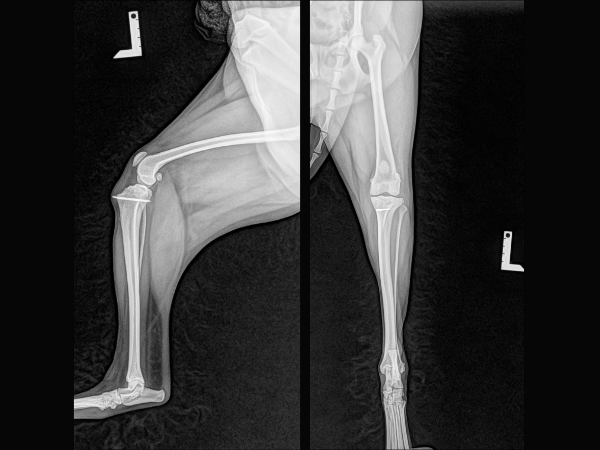

<術後1年後のレントゲン>

再脱臼することなく、膝蓋骨が正常な位置にあります。

▼術前

▼術後